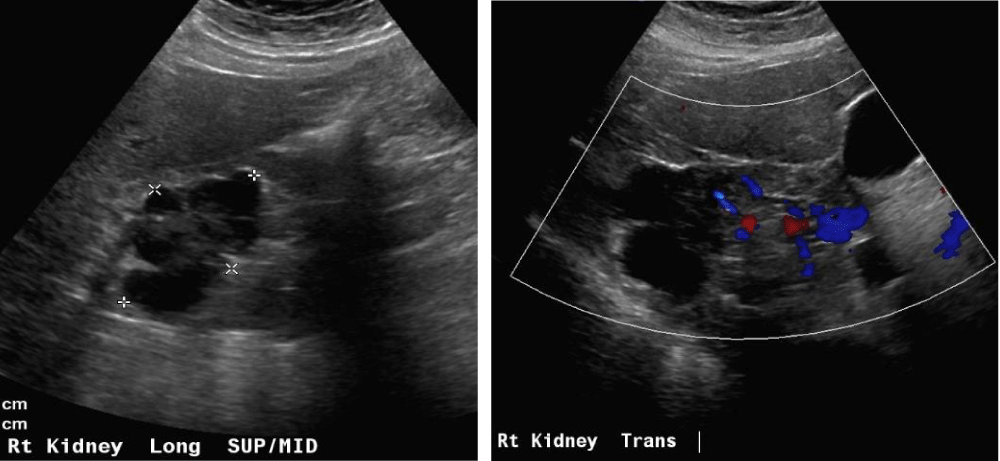

The Bosniak classification system of renal cystic masses utilizes the contrast-enhanced CT depiction of cysts to predict the risk of malignancy. These lesions are then categorized into five groups i.e. either benign (type I and II), likely benign (type IIF), or likely malignant (type III and IV). Simple cyst features distinguishing cysts from tumors or abscesses on the US constitute, round sharp smooth walls, ‘anechoic’ absent echoes in the cyst, (Figures 10 a,b) and a strong posterior wall echo, indicating adequate transmission. When these three criteria are not satisfied, CT is indicated [1-3,5,28-30].

Figure 10a,b: Right cystic mass now with solid components concerning renal neoplasm with increased vascularity.